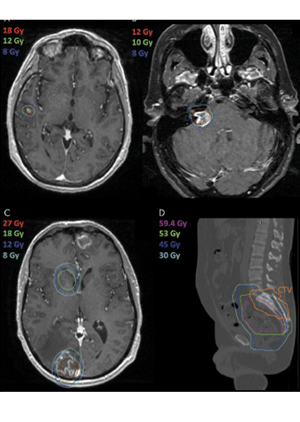

Isodose lines on a treatment planning MR image can be viewed on a picture archiving and communications system to allow radiologists and oncologists to readily know if a lesion received prior radiation treatment. Four example cases are shown in which the prior radiation dose aided in medical decision making. A, A previously treated lesion in the right superior temporal gyrus with SRS to 18 Gy 8 months prior showed residual enhancement at follow-up MRI. However, the new area of enhancement falls all within the 18-Gy isodose line, providing reassurance that the cause is likely radiation treatment effect. B, A right vestibular schwannoma was previously treated with 12 Gy at SRS 9 months prior with follow-up MR image now showing enhancement in the right cerebellopontine angle with increased size. The case was reviewed at our SRS conference, and consensus was made that the lesion shows radiation treatment effect given relation to prior isodose lines. C, A right occipital lesion was seen with enhancement after resection and postoperatively (SBRT) with 27 Gy to the resection cavity 12 months prior. The multidisciplinary team reviewed isodose lines without clear consensus whether the lesion represented treatment effect versus recurrence; consensus was made to try bevacizumab (Avastin) with possible reresection if no response. D, A previously treated colorectal adenocarcinoma to 59.4 Gy 3 years prior presented with sacral spine metastases. The CTV including S1-S3 was viewed on the CT simulation scan in relation to prior isodose lines, without significant prior overlap, giving confidence to proceed with 30 Gy in five fractions to the sacral spine. CTV = clinical target volume, SBRT = stereotactic body radiation therapy, SRS = stereotactic radiosurgery.

Savjani et al, Radiology 2021 ©RSNA 2021